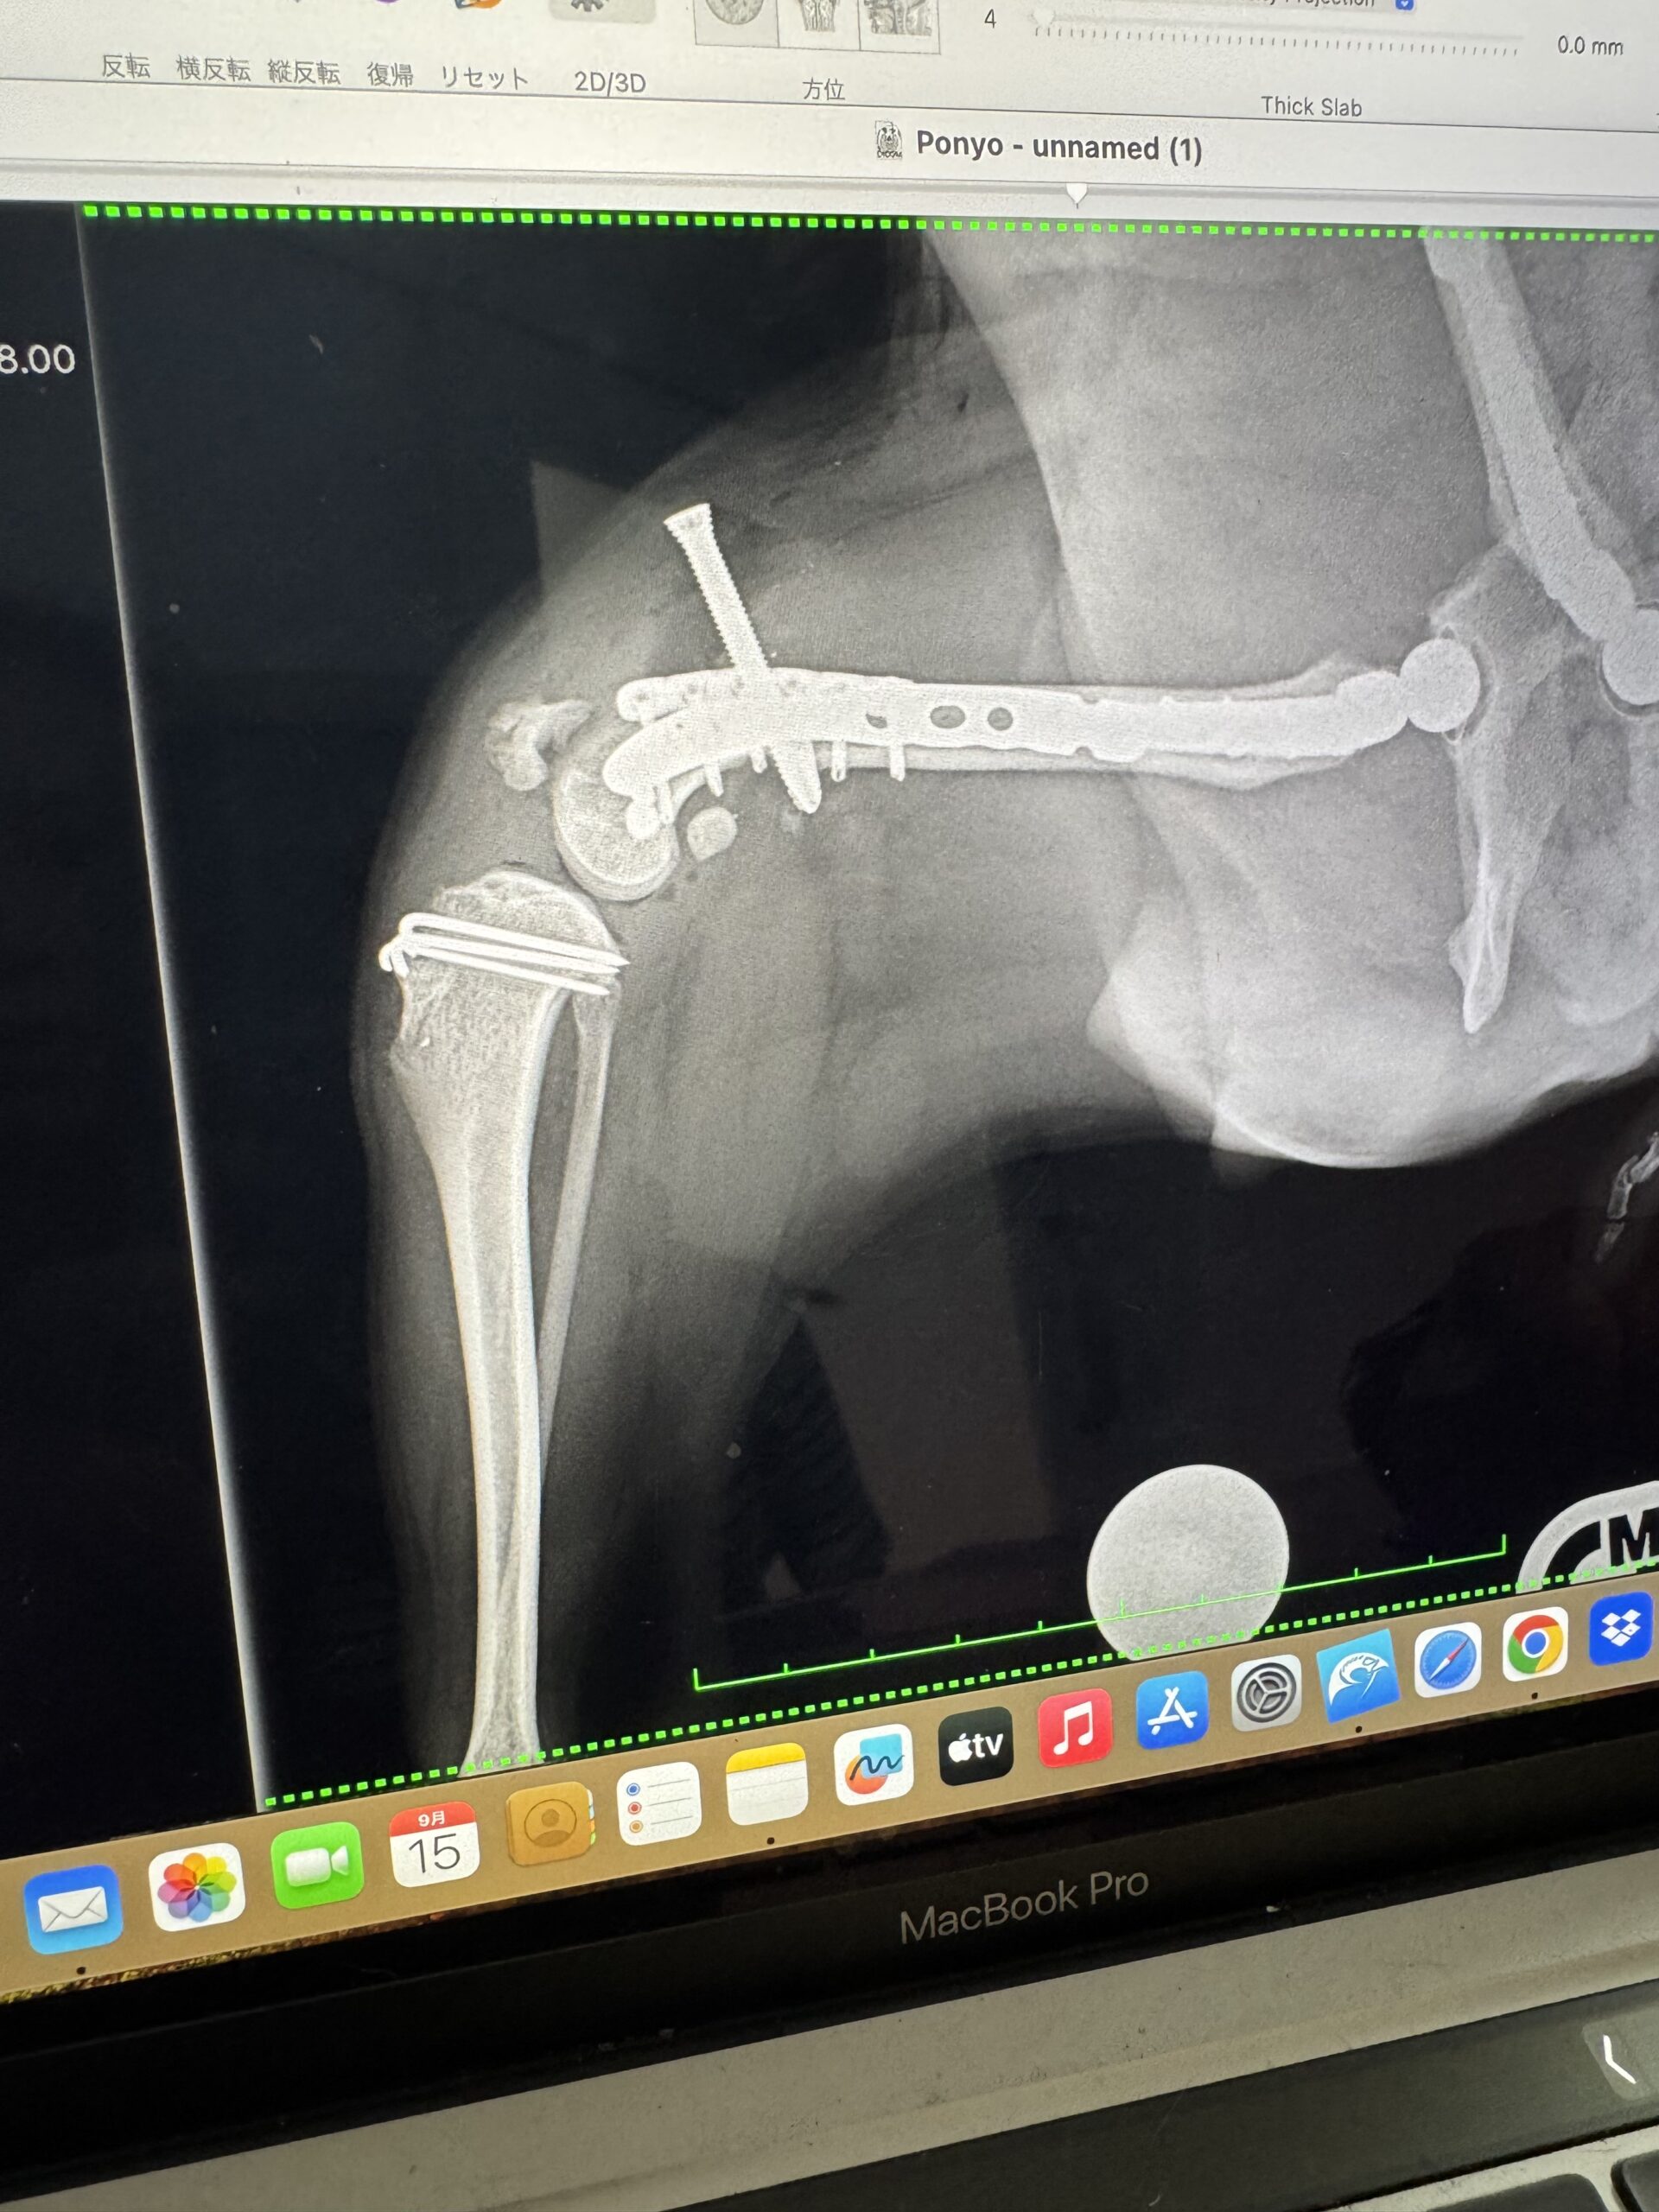

ただ、ぽにょの太ももの筋肉の捻る力が強いため、術後の関節に負担をかけないようアンカーのような長いボルトを入れることとなり、1か月後に20分ほどの手術で抜く方針となりました。

順調に投薬はできていましたが、次の受診で先生の予想通り、手術で入れた人工物に反応が出てきはじめてしまいました。

免疫疾患からみると、人工物は抜ける限りすぐに抜きたい。そうでないと炎症から関節液が溜まって膝のお皿が浮いてしまい再脱臼してしまう。

整形外科的にみると、今抜いたら固着していないのでせっかく手術した足が再脱臼してしまう。

にっちもさっちもいかない、とはまさにこのこと、という綱渡りの状況です。

そのうち後ろの左足の傷からも浸出液が出始め、足をつくこともできないほど痛みも出てきてしまいました。

少し薬を多くして、何とかあと1か月頑張って、抜ける限りのものを抜きましょう、という方針になり、ようやく迎えた手術の日。

11月11日に日帰りの予定で受診をしましたが、薬の量を多くすることで、浸出液も止まり、状況が改善しているはずだった後ろ足の状況がほぼ変わっておらず、その場で術式変更となりました。

予定より多くの人工物を抜く方針になり、手術日が変更となりそのまま入院となりました。